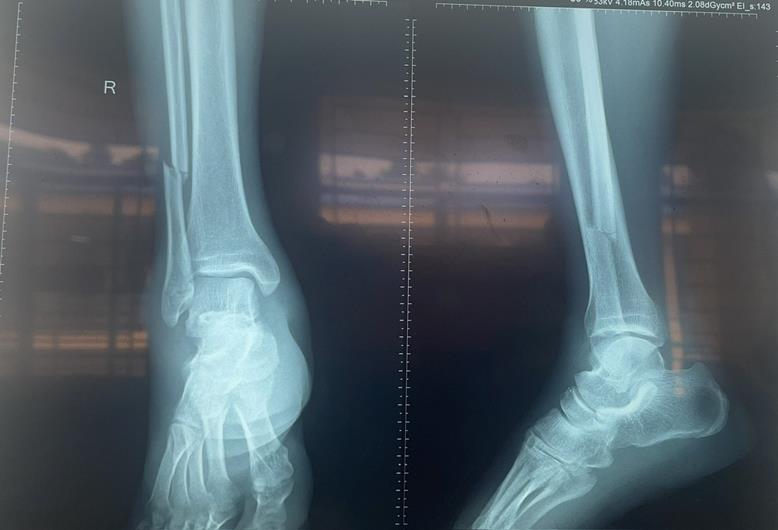

Hình ảnh chụp X-Quang chân phải của bệnh nhân trước (ảnh 1) và sau phẫu thuật kết hợp xương (ảnh 2)

Bệnh nhân nhập viện trong tình trạng sưng đau cẳng chân phải và hạn chế vận động ở cổ chân phải. Sau thăm khám và thực hiện chụp X-Quang, bệnh nhân được chẩn đoán bị gãy xương mác bên phải và được chỉ định phẫu thuật kết hợp xương.